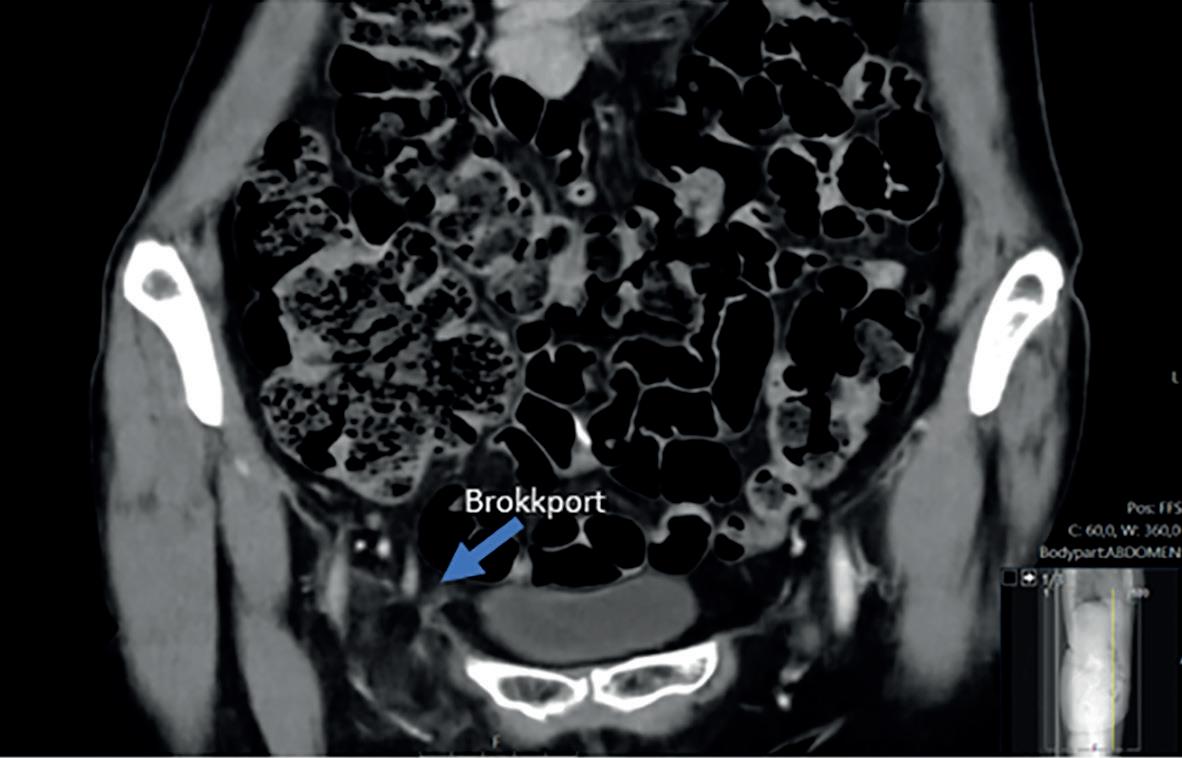

Du er på din femte måned som LIS i kirurgi på et lite lokalsykehus. Du har nettopp kommet på nattevakt og er på vei til akuttmottaket for å tilse flere pasienter som ligger og venter. En 21 år gammel mann er meldt inn med perianal abscess, og på vei inn til ham går du gjennom din mentale sjekkliste før oppmelding til kirurgi. Når du undersøker pasienten mistenker du at han har en abscess, men den sitter ikke der du forventet. Pasientens hud er rød og irritert i midtlinjen mellom nates og har tre små åpninger hvor det tømmer seg blodig, blakket væske. Til venstre for midtlinjen er det en øm, fluktuerende oppfylning på ca. 3 x 3 cm som ligger 10 cm kranialt for endetarmsåpningen. Pasienten er ved god allmenntilstand. Han er afebril, har leukocytter innenfor referanseområdet og CRP 14. På listen din over differensialdiagnoser har du kanskje perianal abscess, hidradenitis suppurativa og pilonidal abscess. Disse tilstandene bør gjenkjennes og diagnostiseres klinisk.

«Kjært barn har mange navn», sies det. Pilonidal sinus, «tvilling» og sakralcyste er begreper som gjerne brukes om hverandre når det snakkes om pilonidal sykdom. Denne artikkelen omhandler sykdomstilstanden som befinner seg i midtlinjen, nærmere bestemt glutealkløften, eller rima internates (rumpesprekken) om du vil. For ordens skyld nevnes det at tilstanden også kan finnes i eksempelvis navlen, hodebunn og mellom fingrene. Insidensen av pilonidal sykdom estimeres til 26 per 100.000 innbyggere (1). Tilstanden er ervervet og debuterer oftest i 20-årsalderen. Den ses sjelden etter fylte 40 år. Begge kjønn affiseres, menn to til tre ganger hyppigere

enn kvinner. Risikofaktorer er overvekt, lokalt traume, dyp glutealkløft, hirsutisme, stillesittende livsstil og polycystisk ovariesyndrom (PCOS)(1-3). Tilstanden kan debutere uten at noen av de ovennevnte risikofaktorer er til stede.